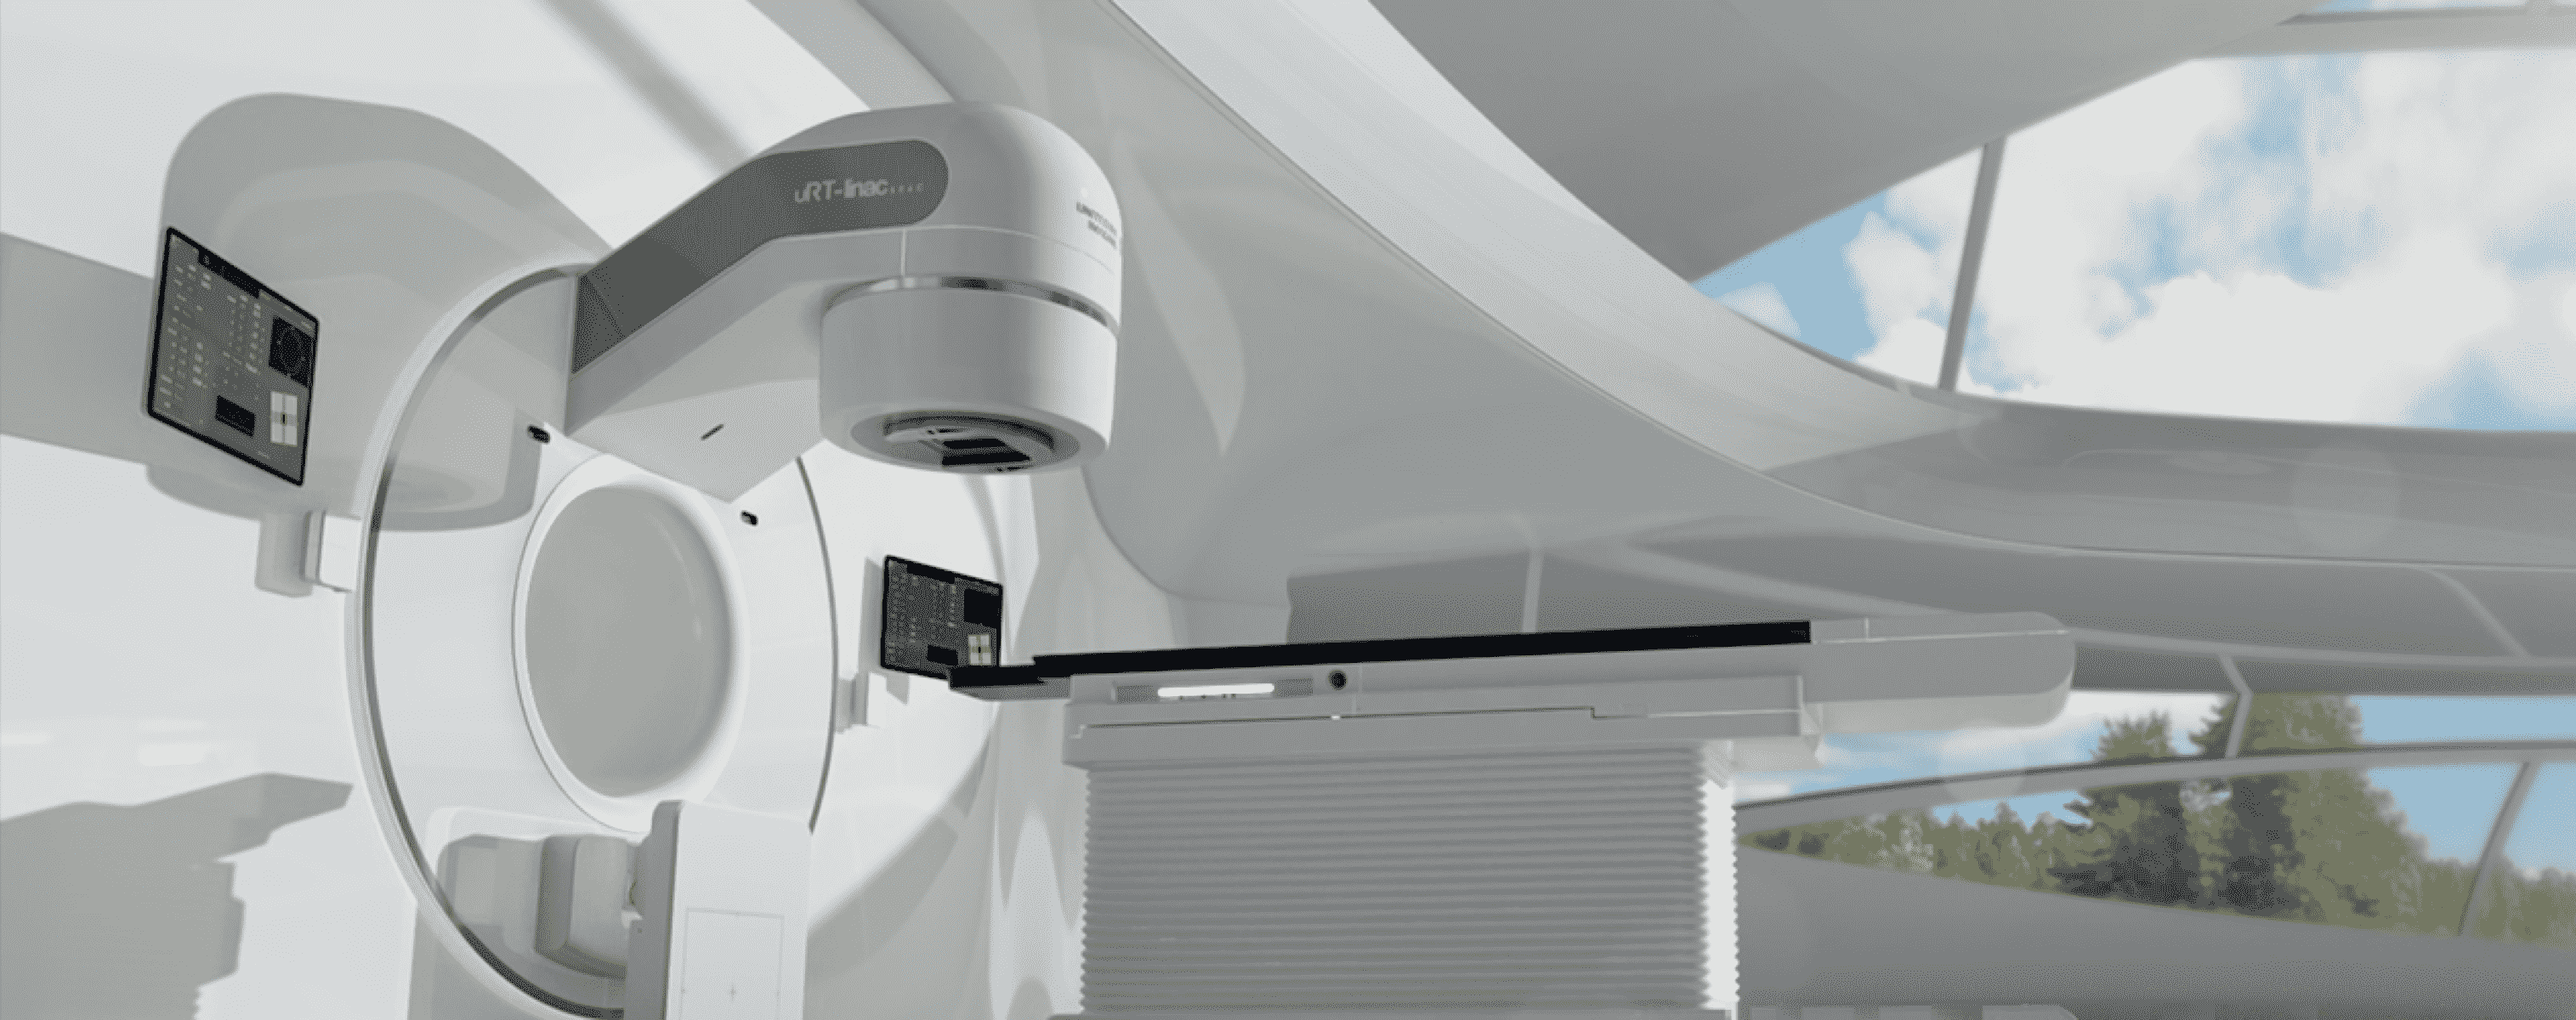

揭秘放疗「狙击枪」——加速管

揭秘放疗「狙击枪」——加速管

放疗是世界公认的肿瘤最佳治疗手段之一,加速管对放疗设备的精准度起到关键性作用。它犹如一把利剑,把像瀑布一样滔滔不绝的电子光束瞬间切成均匀的电子团,最后「变身」为「枪管」,将子弹般的电子团送上「枪膛」,一颗颗不间断地精准直击隐匿在身体中的癌细胞。

2015年7月,在Bunker内,第一道高能X射线从自研加速管中射出,精准打在靶区上。经数次验证各项指标皆可达到可量产水准——联影医疗首个自主研发且可实现量产化的医用加速管由此诞生。

以此为基础,世界首款一体化CT-linac 506c问世,目前,已在上海复旦大学附属肿瘤医院、中山大学肿瘤防治中心、武汉中南医院等知名大三甲医院投入使用,为上万位病人提供精准放疗。